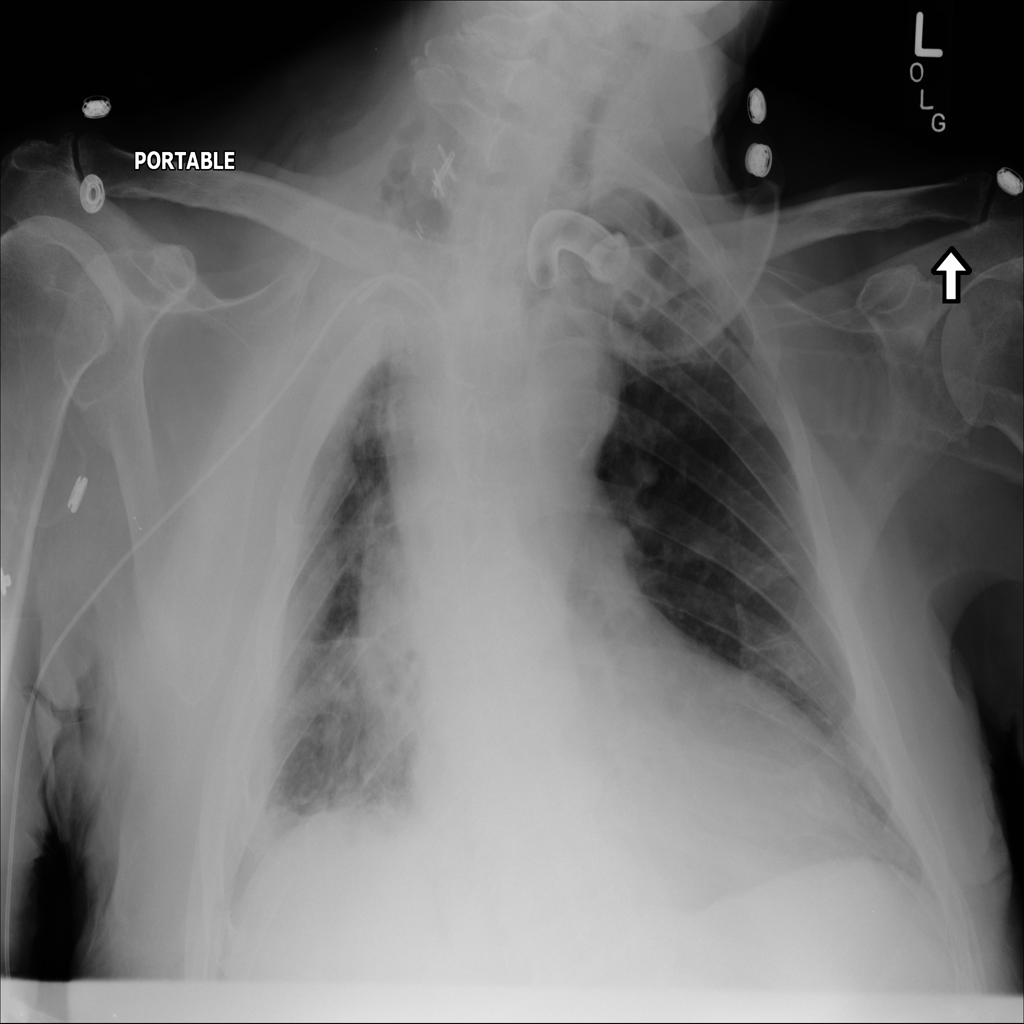

Mass

A mass is a larger focal opacity or lesion seen on the image. It is a descriptive finding that can have several causes and usually needs more imaging or clinical context to characterize.

PAT-C0E5 · IMG-001Mass

PAT-C0E5 · IMG-001

PA